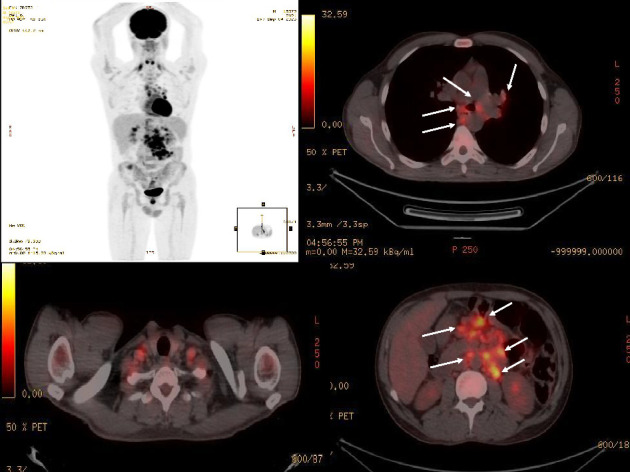

Mycobacterium genavense was first identified in a patient with HIV. Here, we describe a 40-year-old man with prolonged fever and mediastinal and abdominal lymphadenopathy, who was initially misdiagnosed with sarcoidosis. A molecular study was conducted after mycobacterium was isolated from a lymph node biopsy, leading to the identification of M. genavense. The identification of this microbe, along with recurrent oral candidiasis and varicella skin lesions, raised suspicion of an immunodeficiency disorder, which ultimately resulted in an HIV diagnosis. Concurrently, the patient experienced polyradiculopathy caused by cytomegalovirus. This case highlights that after identifying a granuloma in tissue, a comprehensive investigation to exclude infectious causes using microbiological and molecular methods is crucial.